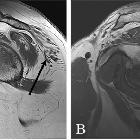

fatty infiltration of the teres minor in patients with shoulder pain? A review of 7,367 consecutive MRI scans. Sagittal T1-weighted MRI demonstrating fatty infiltration of the deltoid muscle in 2 patients